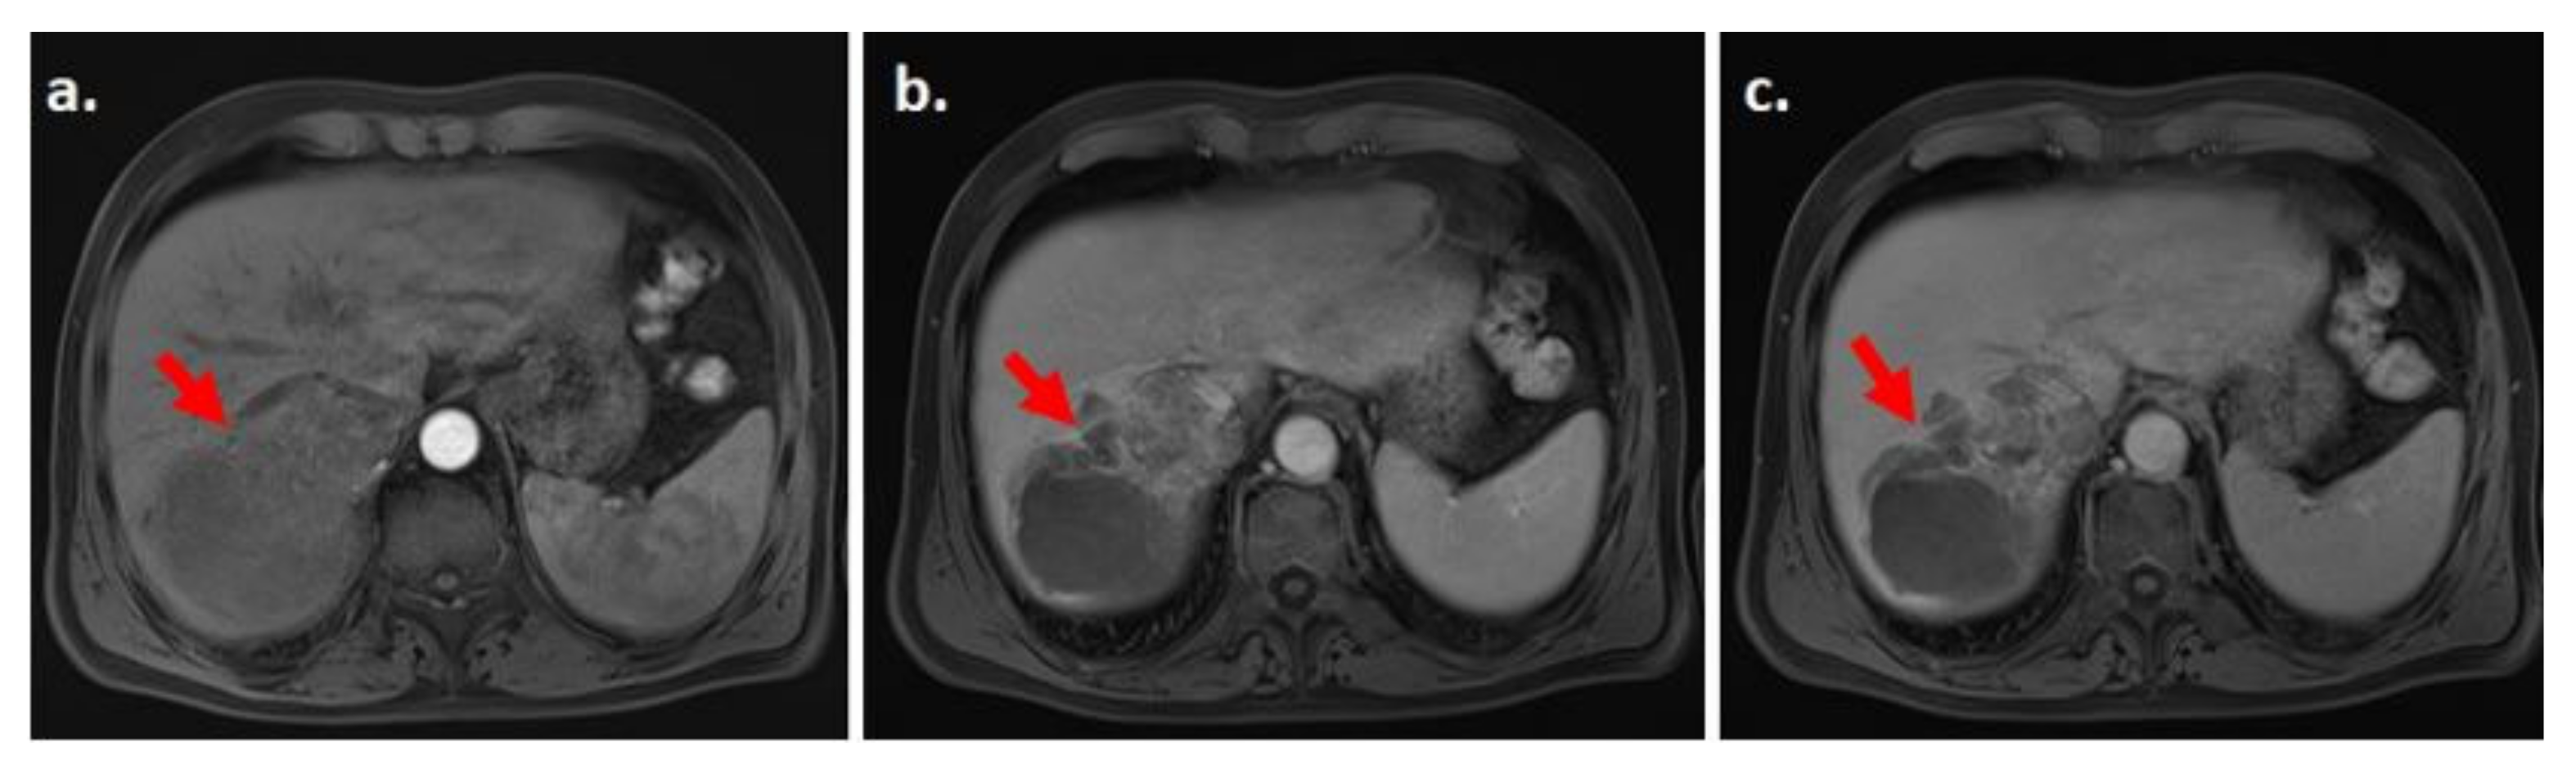

3.4. Enhancing Capsule

- The mosaic architecture and nodule in nodule (both considered AF which favor HCC in particular)

- Nodule in nodule architecture (favors HCC)

- Mosaic architecture (which equally favors HCC)

- For mosaic and nodule in nodule lesions, if APHE cannot be demonstrated by CT/MRI, we recommend additional imaging by CEUS, which is more sensitive in depicting APHE (and subsequently possibly classifying the lesion as LI-RADS 5).